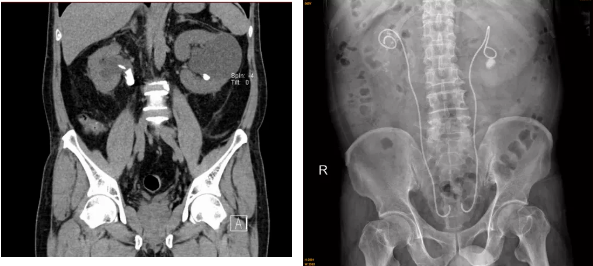

原来在5月初,69岁的郭叔因左侧腰痛伴少尿4天,自行服药效果不佳来到我院。医院检查时发现,其双侧输尿管结石梗阻,血肌酐水平超出正常高限十多倍,达到1375.8μmol/L。(正常范围:44μmol/L-133μmol/L,血肌酐的升高就说明出现了肾功能不全)。

泌尿外科林茂副主任医师、张俊文主治医师考虑患者系泌尿系结石阻塞尿路引起的急性肾衰竭。先为患者行右肾造瘘术解除梗阻恢复,随后在其右侧输尿管上段开展狭窄扩张术、右侧输尿管镜下碎石取石术和双侧输尿管“双J”管内置术。

术后,郭叔的尿量逐渐恢复正常,血肌酐指标水平明显下降至200μmol/L左右。